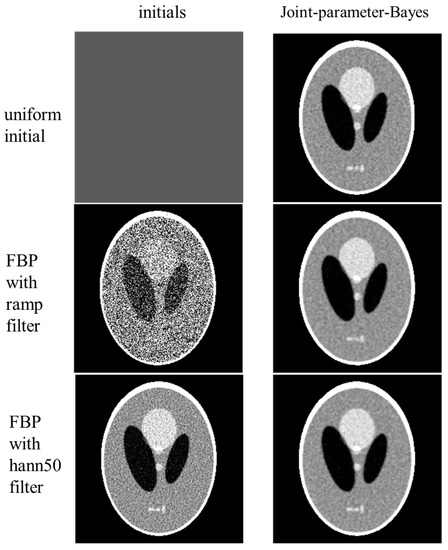

3.1.3. Stability Investigation

- Effect of Initialization

- Effects of Variance Normalization